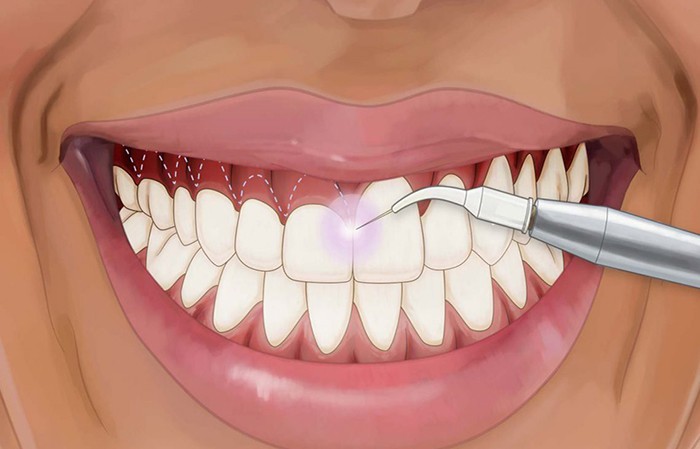

درمان عفونت و التهاب و ورم لثه

در این مقاله به عوارض، علل و راههای درمان عفونت و التهاب و ورم لثه پرداخته خواهد شد. همراه ما باشید تا با درمان این بیماری ها آشنا شوید.